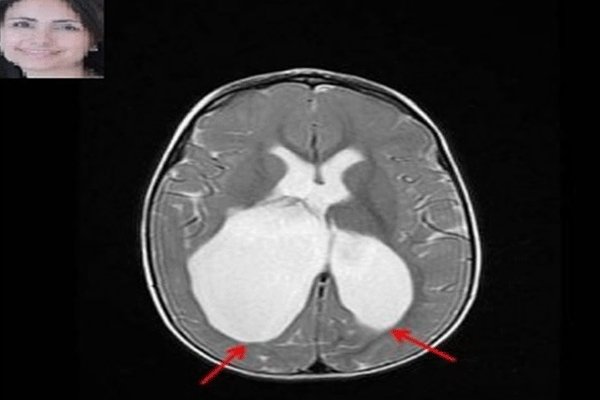

فلج مغزی به مجموعه ای از علائم عصبی اطلاق می شود که به اختلال در حرکت و وضعیت کودک منجر می شود.

فلج مغزی به مجموعه ای از علائم عصبی اطلاق می شود که به اختلال در حرکت و وضعیت کودک منجر می شود. مطالعات اخیر نقش پایه ای ژنتیک را در بروز فلج مغزی ثابت کرده و مانند بیشتر بیماری های نوروژنتیک، نحوه وراثت چند عاملی (مولتی فاکتوریال) برای آن مطرح شده است.

محققان کانادایی به سرپرستی دکتر «مریم اسکویی»، متخصص مغز و اعصاب بیمارستان کودکان مونترال کانادا موفق به کشف عامل ژنتیکی فلج مغزی شدند.

مطالعات محققان نشان می دهد، مولفه های ژنتیکی در بروز فلج مغزی بیش از تصورات پیشین نقش دارند. در این مطالعه به چگونگی تعامل عوامل خطر ژنتیکی نیز پرداخته شده است.

نتایج این مطالعه می تواند باورهای گذشته درباره عوامل فلج مغزی را تغییر دهد زیرا پیش از این تصور می شد عفونت و خفگی هنگام تولد عاملی برای فلج مغزی هستند، به همین دلیل توجهی به آزمایشات ژنتیکی پیش از بارداری نمی شد.

محققان در مطالعات گذشته چندین عامل خطرساز مرتبط با بارداری از جمله زایمان زودرس، رشد غیر طبیعی، قرار گرفتن در معرض عفونت و کمبود اکسیژن در هنگام تولد را شناسایی کرده بودند. فلج مغزی، در توانایی حرکت کردن اعضای بدن و حفظ تعادل اثر می گذارد.